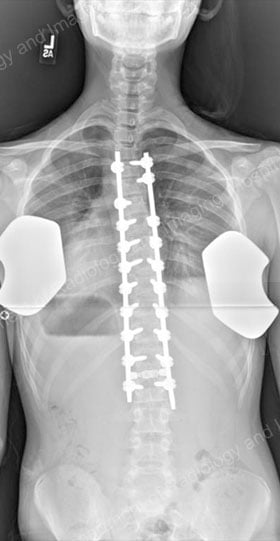

There are different surgical methods, but the most common type of surgery is a posterior spinal fusion with instrumentation (artificial implants). In this procedure, the orthopedic surgeon makes an incision from the back and essentially "welds" the vertebrae together using bone chips.

The spine is then healed in alignment by hooks or screws and rods. Once the fusion is complete, the implants no longer serve a function but are left in place to avoid the need for additional surgery. Some patients may be candidates to have a surgical fusion using minimally invasive spine surgery.

Postsurgical X-ray images of the corrected spine, with a posterior (rear) view and a lateral (outer side) view.